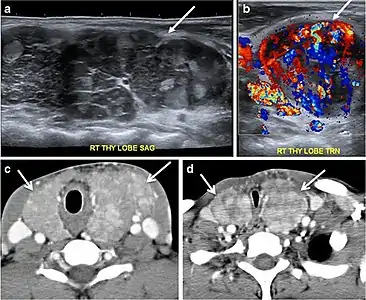

Fig. 8. A 48-year-old male patient post total thyroidectomy with PTC recurrence. a Transverse greyscale ultrasound of the neck demonstrates a left thyroid bed heterogeneous, predominantly hypoechoic irregular lesion with calcifications (white arrow). b A spot image of iodine 123 total body scan of the neck demonstrate a focus of abnormal radiotracer uptake at the left thyroid bed (Black arrows) between the annotated markers. c Enhanced axial CT scan of the neck demonstrates an enhancing large left thyroid bed mass (white arrow) with no calcifications. The lesion exerts a mass effect on the oesophagus (black arrow) and is inseparable from the trachea.[1]

Fig. 9. A 58-year-old male patient with persistence PTC at thyroid bed with hypervascular nodal metastasis. a–c Transverse greyscale and colour Doppler neck ultrasound demonstrate hypoehoic soft tissue in the left thyroid bed (white arrow in a). There are a heterogeneous enlarged lymph nodes at level 2 and 3 with markedly increased vascularity (white arrow in b and c). d–f Enhanced axial CT images of the neck demonstrate a 2.7 × 1.4 cm hypodense soft tissue lesion anterior to the left carotid sheath (white arrow). There are left-sided enhancing abnormal and enlarged lymph nodes at cervical level 2 and 3 (black arrows).[1]